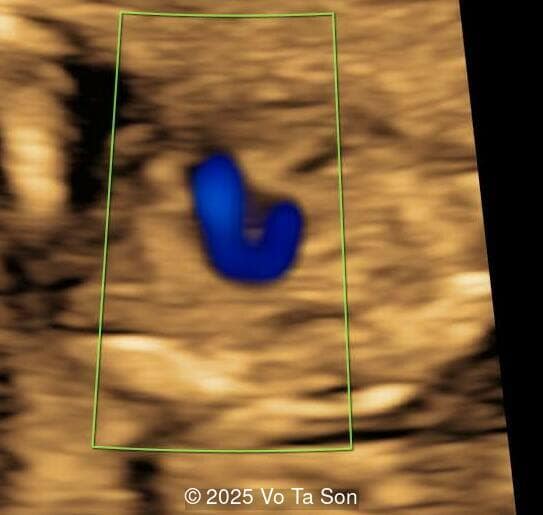

- Right aortic arch